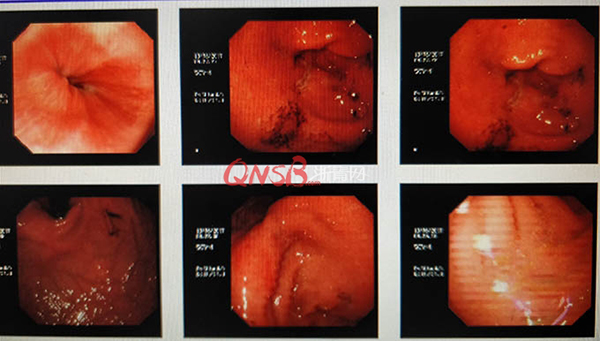

檢查結(jié)果出來后,小周大吃一驚,本以為自己的胃很健康,卻不想胃粘膜廣泛充血糜爛,長了兩個巨大的潰瘍(直徑大于2厘米),還有出血和咖啡色血痂。